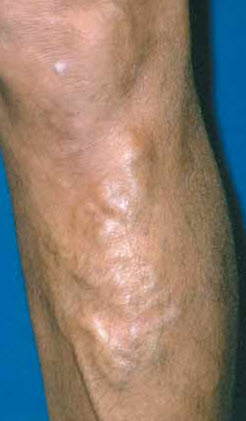

Chronic venous insufficiency. This is characterized by edema, lipodermatosclerosis, stasis dermatitis, and healed or active venous ulcerations. In patients with lipodermatosclerosis, the skin may initially have a pinkish hue (Figure 3), which becomes progressively darker. Eventually, a brownish discoloration develops (Figure 4). Stasis dermatitis, or stasis eczema, is an exacerbation of this process (Figure 5). This inflammatory reaction must be distinguished from cellulitis, because antibiotics are not effective in treating stasis dermatitis.